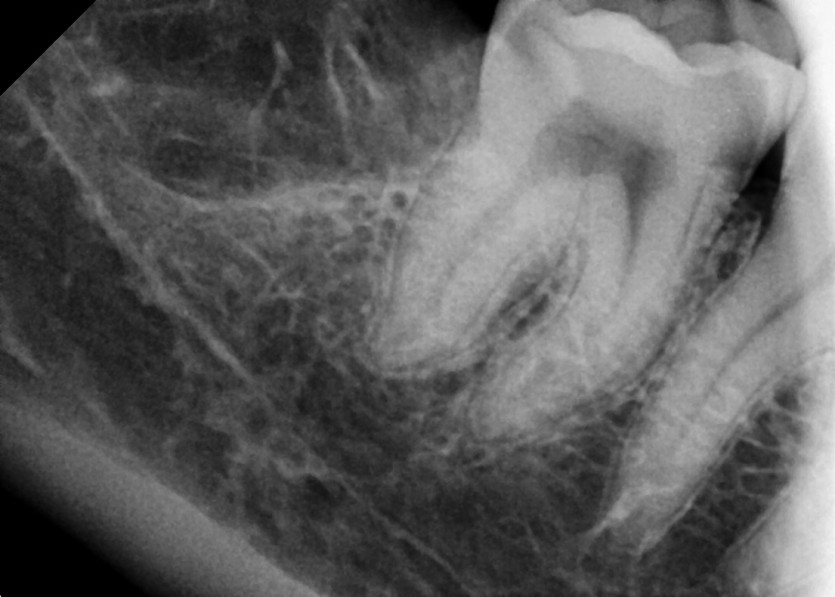

#18,28,38,48 사랑니 발치

구강 외과 전문의가 당일 발치했습니다.